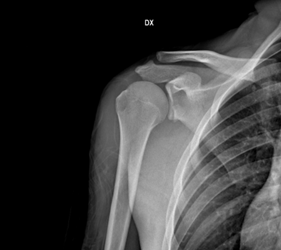

Una recente review evidenzia come dopo la riparazione artroscopica sec. Bankart, i pazienti abbiano evidenziato un tasso di recidiva di lussazione significativamente inferiore rispetto ai pazienti trattati conservativamente (7,5% vs 53,0%), ugualmente per l’incidenza di sublussazione post-op (3,1% vs 24,2%), il test di apprensione positivo (7,3% vs 25,8%) ed in particolare ha evidenziato un ritorno all’attività sportiva superiore nei pazienti sottoposti a trattamento chirurgico (83.5% vs. 66.0%).

La recente Letteratura suggerisce quindi come il trattamento chirurgico fornisca, in gruppi di pazienti selezionati, risultati migliori rispetto al trattamento conservativo in termini di rischio di recidiva e scores clinici.

La strategia di trattamento deve quindi essere individualizzata considerando tutti gli elementi coinvolti, per ridurre il rischio di recidiva, favorendo il ritorno allo sport ed alla funzionalità articolare.